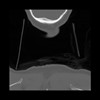

13 P.BLANDAS,,Coronal,2.000,P.BLANDAS,Coronal,